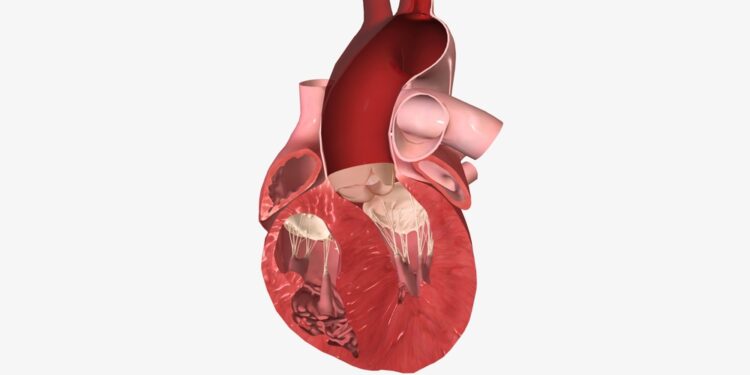

Ventrikulinė tachikardija – tai širdies ritmo sutrikimas, kai širdis pradeda plakti dažniau nei 120 kartų per minutę, ir šis ritmas kyla apatinėse širdies kamerose – skilveliuose, o ne įprastu elektros keliu. Tai lemia, kad širdis nebespėja prisipildyti krauju tarp susitraukimų, todėl organizmas gauna mažiau deguonies nei reikėtų.

Pagrindinė priežastis – nenormalūs elektros impulsai širdies skilveliuose, dėl kurių signalai iš pagrindinio širdies ritmo generatoriaus (sinusinio mazgo) nebegali valdyti širdies ritmo. Įprastai ši problema atsiranda dėl kitų širdies ligų.

Kaip ventrikulinė tachikardija veikia organizmą?

Dėl labai greito širdies ritmo tarp plakimų nebelieka laiko, kad skilveliai užsipildytų krauju. Organizmas į tai reaguoja: sumažėja audinių aprūpinimas deguonimi, krinta kraujospūdis, gali dingti sąmonė ar prasidėti dusulys. Tokį procesą būtų galima palyginti su trumpu autobuso sustojimu stotelėje, kai keleiviai nespėja įlipti – organizmo ląstelės tiesiog lieka be reikalingų medžiagų.